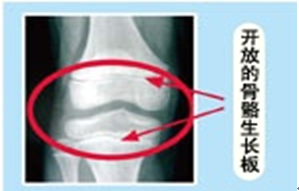

变声和月经是标志孩子进入青春期发育后期的标志,即骨骼生长区(骨骺)已经接近闭合,身高开始进入停长倒计时。